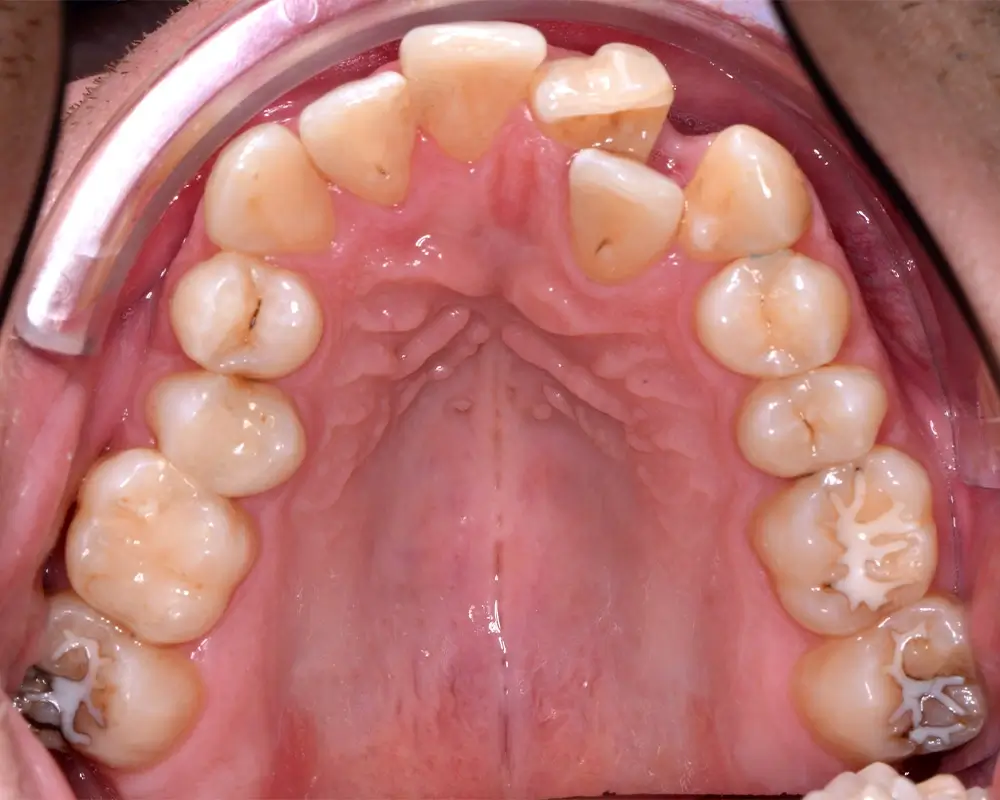

Кейс 4

Бажанова Ольга Валерьевна

Количество кап ВЧ 35

Количество кап НЧ 35

ДО

ПОСЛЕ